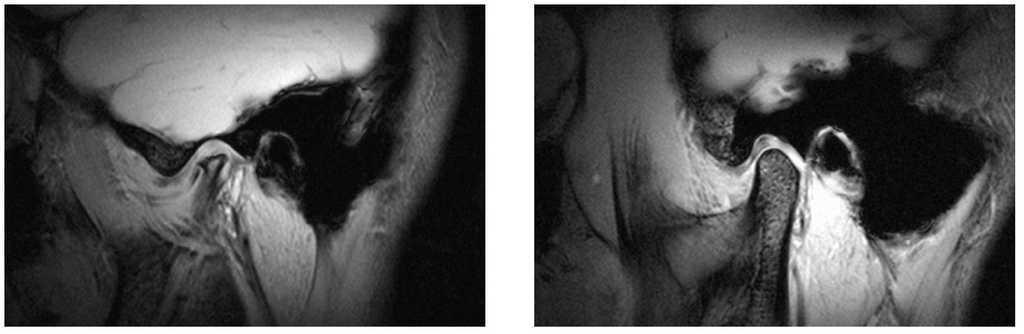

Artrosis de la ATM (fig. 9)

Figura 9. Artrosis de la ATM (derecha: cóndilo normal). Si el cuadro se acompaña de dolor se trata de una artrosis de la ATM en fase activa. En la exploración clínica, los movimientos de la articulación temporomandibular se acompañan a menudo de un ruido de fricción.

La artrosis se acompaña de un cambio de forma del cóndilo articular y es un hallazgo relativamente frecuente en muestras aleatorias representativas de pacientes5. En esta situación se constata a menudo una discrepancia entre el diagnóstico y la sintomatología, es decir, muchos pacientes presentan signos claros de artrosis (en pruebas de imagen), pero no refieren ningún tipo de molestia. Por el contrario, otros pacientes sólo muestran signos leves (en pruebas de imagen), pero presentan una sintomatología florida. Las alternativas terapéuticas son limitadas: tratamiento con férulas, farmacoterapia y/o procedimientos invasivos. En un estudio reciente se ha demostrado la eficacia de los procedimientos invasivos8, aunque se deberían reservar para el tratamiento de pacientes con limitaciones importantes y dolor intenso. Las alternativas conservadoras, como el tratamiento con férulas, se pueden utilizar solas o en combinación con procedimientos invasivos4 (como el «lavado articular»). En la consulta dental, la combinación de una férula y farmacoterapia (por ejemplo con ibuprofeno 400 mg, asociado a un protector gástrico si procede) ha proporcionado buenos resultados. En general, las alteraciones artrósicas de la ATM evolucionan por brotes, por lo que una artrosis inactiva puede experimentar en cualquier momento una agudización y pasar a una artrosis activa. En un estudio reciente21 se estableció la hipótesis según la que la reconstrucción de un apoyo posterior en estos pacientes podría favorecer la mejoría de las molestias. Estos resultados se han visto confirmados por un estudio reciente publicado en revistas de renombre internacional25: la falta de piezas en el sector posterior, sobre todo en varios cuadrantes, incide en una mayor prevalencia de trastornos funcionales.